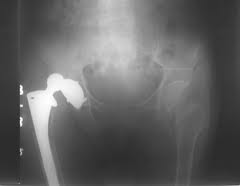

Wear of the Plastic Polyethylene Socket

starts from the day of surgery. The plastic socket is the weakest link in the implant. The rate of plastic wear against a metal ball is about 0.1 millimeters per year, but is more rapid in very active patients. “Cross-linked” polyethylene promises a wear rate about half that of regular poly. Plastic wear against a ceramic ball is much less in the lab, but this has not yet been shown to be true in the human body. Metal-on-metal bearings will never wear out. Nor will ceramic-on-ceramic implants, but there is a 1/20,000 risk of fracture of the ceramic ball. Dr. Huddleston uses and recommends metal on metal implants, or ceramic on ceramic implants for those patients who want them, and have a life expectancy of more than fifteen years. In all others he uses cross-linked polyethylene. (“Marathon” Polyethylene from Johnson & Johnson). Paradoxically, Dr. Huddleston may use a large-head metal-on metal implant in older patients with loose ligaments for the stability it confers and not for its wear properties.

Allergy to the metal parts

About 15% of the population has skin sensitivity to some metals. All metal implants release some metal ions into the body. However, reports of proven allergies to metal implants are surprisingly rare. You should notify Dr. Huddleston if you believe you have a metal allergy. People who know they have metal allergies should be tested with extracts of the various metal components of the implant prior to surgery. The tests are not reliable, so they are only performed if a metal allergy is suspected. Allergy to the plastic parts has never been reported. Small particles of plastic or metal from the implant may cause a “foreign body” reaction in the bone, but this is not a true allergy. Some patients with metal implants have had temporary, mild skin rashes, while some have had severe rashes that resolved only with removal of the implant. If you are known to be sensitive to nickel, chromium or cobalt you should probably have a titanium implant, even though there have been reports of allergy to titanium as well.

ALVAL

Patients frequently enquire if the body can “reject” the hip implant. Until recently the answer has been an emphatic “no”. The body does react adversely to the microscopic particles that abrade off a plastic socket, but the reaction is not rejection but a “ histiocytic response” to foreign particles, which can cause the implant to loosen.

Since the advent of large-head, metal on metal hip replacements, a new ominous entity has been identified which has been given the clumsy name of ALVAL (Aseptic Lymphocytic Vasculitis Associated Lesions). A Delayed Type of metal Hypersensitivity (DTH) is induced due to high concentrations of Cobalt and Chromium ions that build up around the joint. This leads to painful inflammation in the joint (“Lymphocytic Vasculitis”). Sometimes necrotic inflammation tissue combined with proteins builds up around the hip and into the pelvis, forming so-called “pseudo-tumors” which can be seen on CT, ultrasound or MRI scans, and can be a perplexing diagnosis for the un-initiated. ALVAL is rare. It is seen most frequently in women.